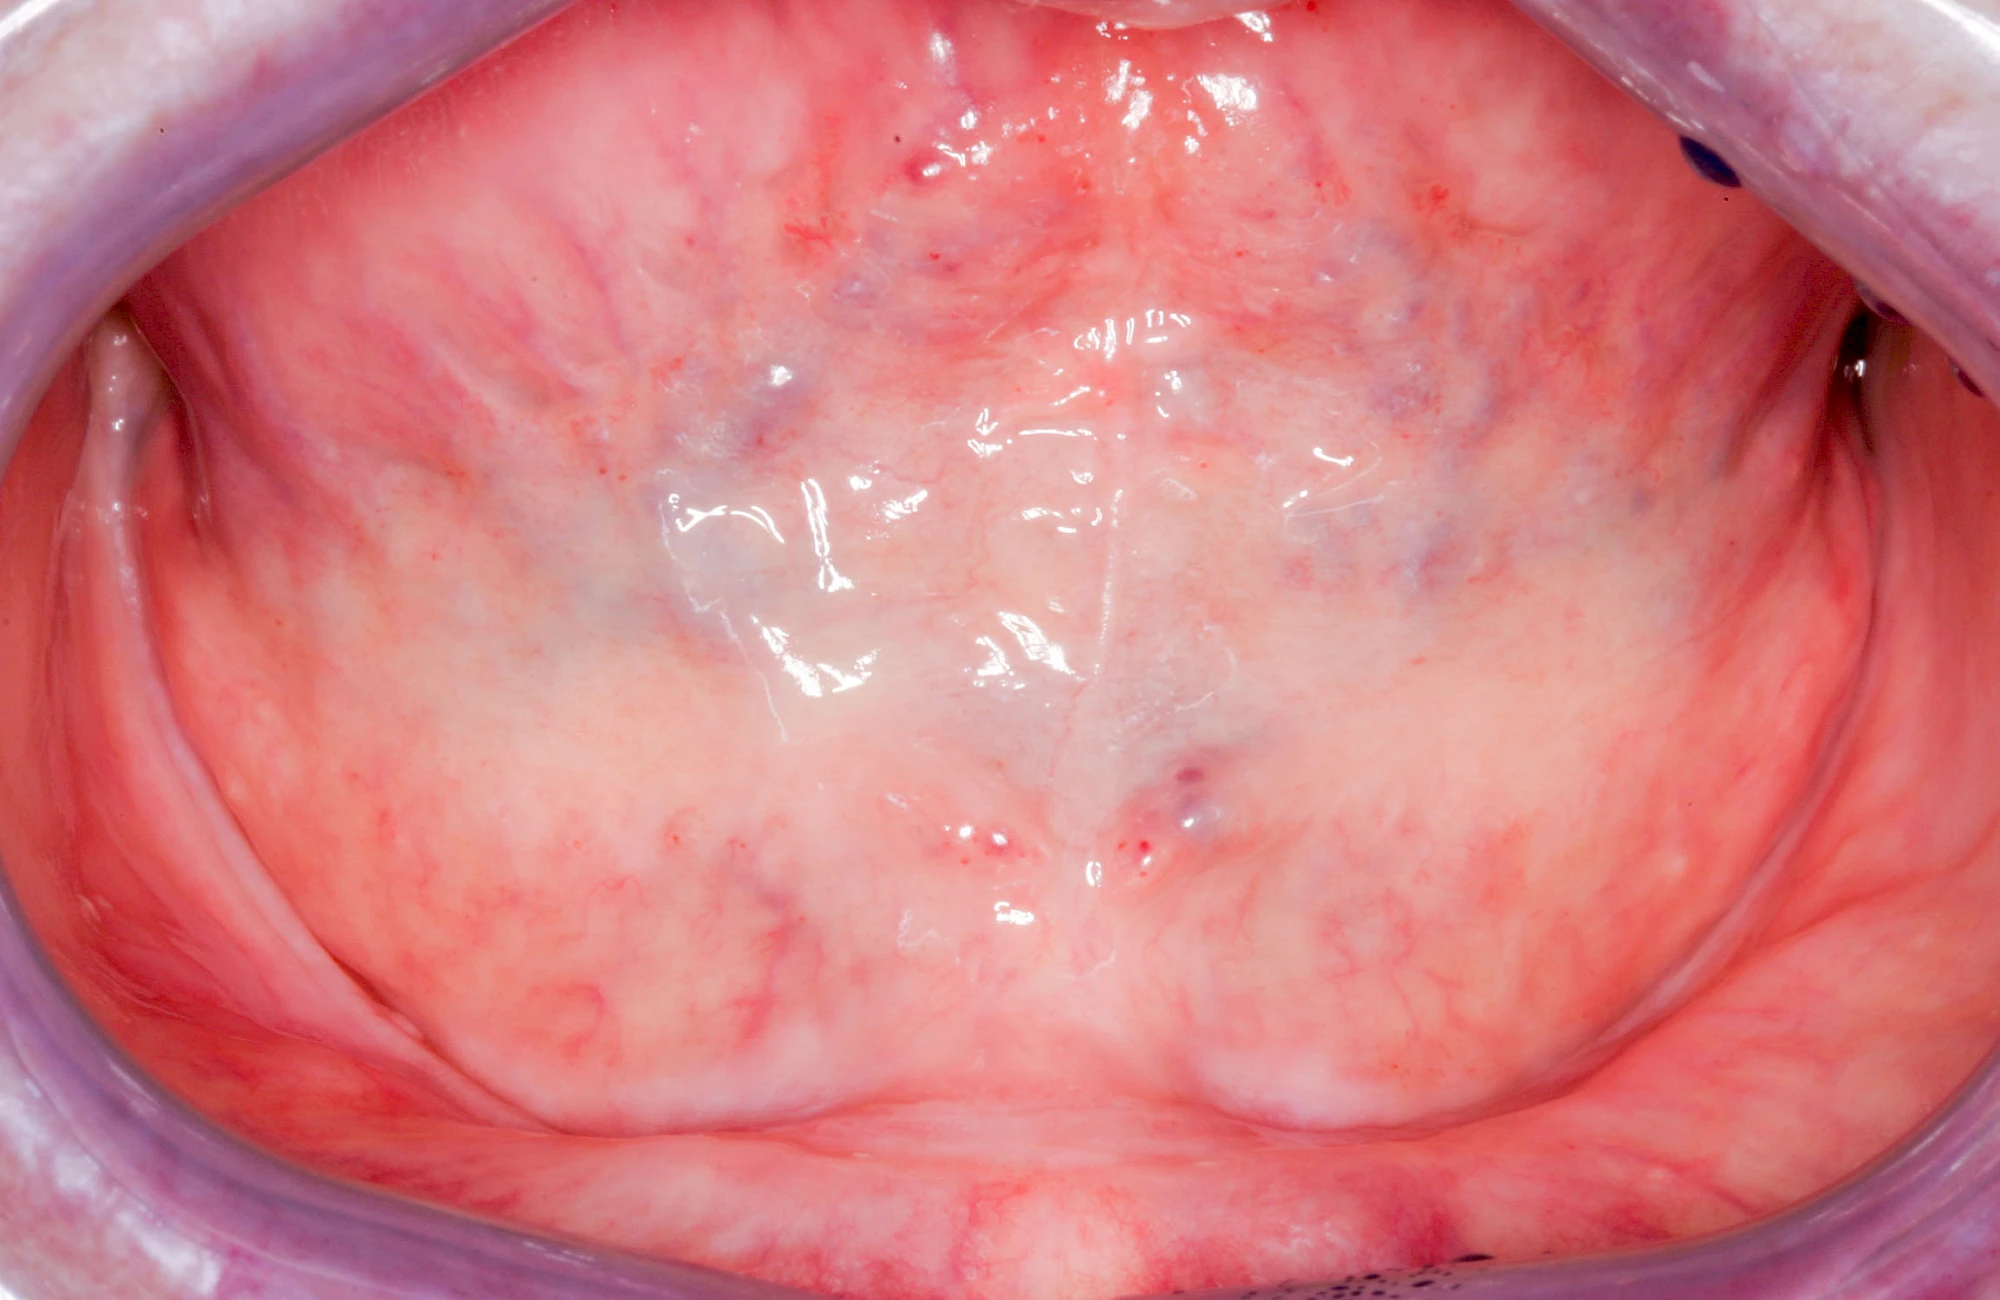

Gehen die Zähne verloren, baut häufig auch der Kieferknochen ab (Knochenschwund). Die Geschwindigkeit und das Ausmaß des Knochenschwundes ist von vielen Faktoren abhängig. Neben der genetischen Veranlagung spielen auch Überbelastungen in Folge, z. B. bei ständigem Knirschen oder Pressen, eine Rolle. Auch wenn Zahnprothesen Tag und Nacht getragen werden, kann die ständige Belastung der Schleimhäute und des Knochens den Knochenschwund beschleunigen.

In seltenen Fällen schwindet nur der Knochen, aber nicht die bedeckenden Schleimhäute. In diesen Fällen spricht man von einem sogenannten "Schlotterkamm".